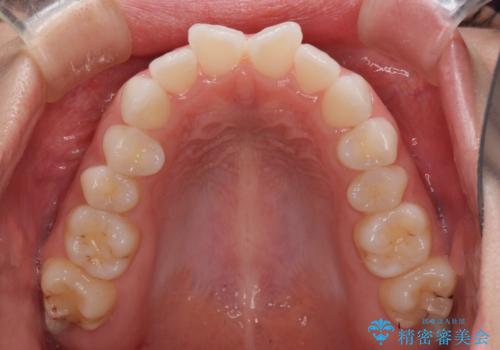

- 海外留学を前に上下のデコボコと奥歯の咬み合わせを改善したいとのことで来院された患者様です。

治療開始から4ヶ月ほどで概ね歯列が整い、その後の3ヶ月で細かい部分を仕上げていきました。

短期間で綺麗に仕上がり、患者様には大変満足していただきました。